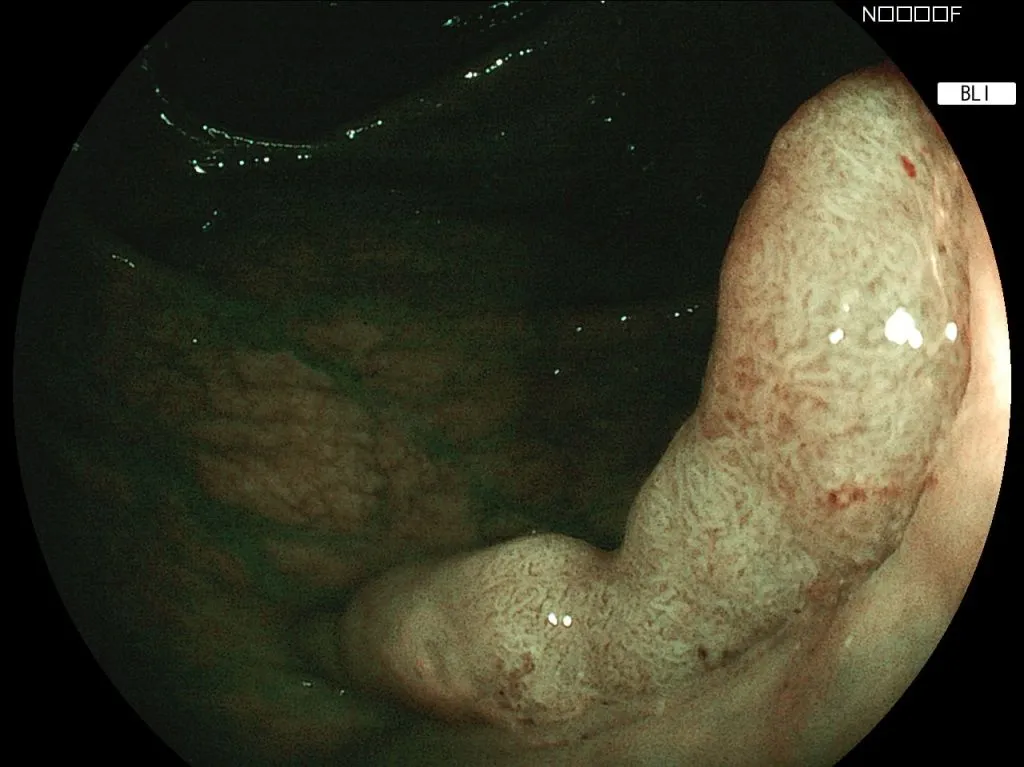

a) изображение в белом цвете                                                  б)изображение технология BLI

Плоско приподнятое эпителиальное образование тип 0-2a., что видно на режиме Bli, где четко видны округлые и овальные ямки и сосудистый рисунокcolonminlocal.png

Аденома.

Патологогистологическое заключение от 12.11.20. case_Bli101_bli_zoom_EndoExpert.ru.jpg

Оптимально выполнять осмотр последовательно в белом свете, затем BLi, затем LCI.

Технология позволяет видеть без изменения белого цвета четко поверхность и сосудистый и ямочный рисунки